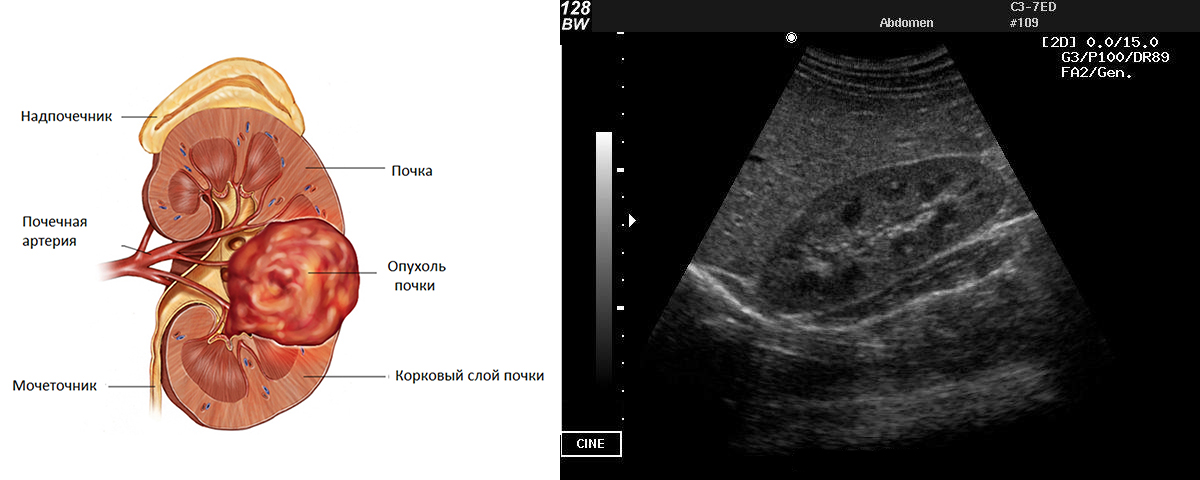

| Опухоль | Неоднородное образование с неровными краями. |